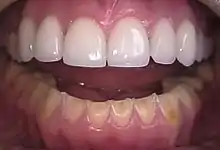

The erosion on the lower teeth was caused by bulimia. For comparison, the upper teeth were restored with porcelain veneers.[13]

People with bulimia are at a higher risk to have an affective disorder, such as depression or general anxiety disorder. One study found 70% had depression at some time in their lives (as opposed to 26% for adult females in the general population), rising to 88% for all affective disorders combined.[27] Another study in the Journal of Affective Disorders found that of the population of patients that were diagnosed with an eating disorder according to the DSM-V guidelines about 27% also suffered from bipolar disorder. Within this article, the majority of the patients were diagnosed with bulimia nervosa, the second most common condition reported was binge-eating disorder.[28] Some individuals with anorexia nervosa exhibit episodes of bulimic tendencies through purging (either through self-induced vomiting or laxatives) as a way to quickly remove food in their system.[29] There may be an increased risk for diabetes mellitus type 2.[30] Bulimia also has negative effects on a person's teeth due to the acid passed through the mouth from frequent vomiting causing acid erosion, mainly on the posterior dental surface.